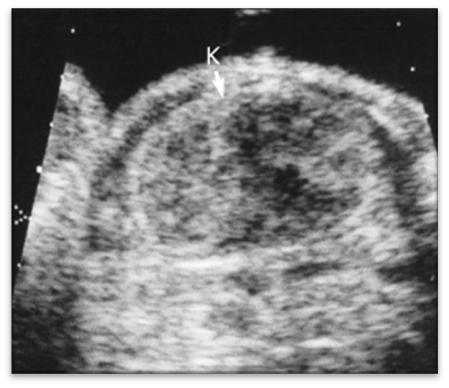

hydronephrosis